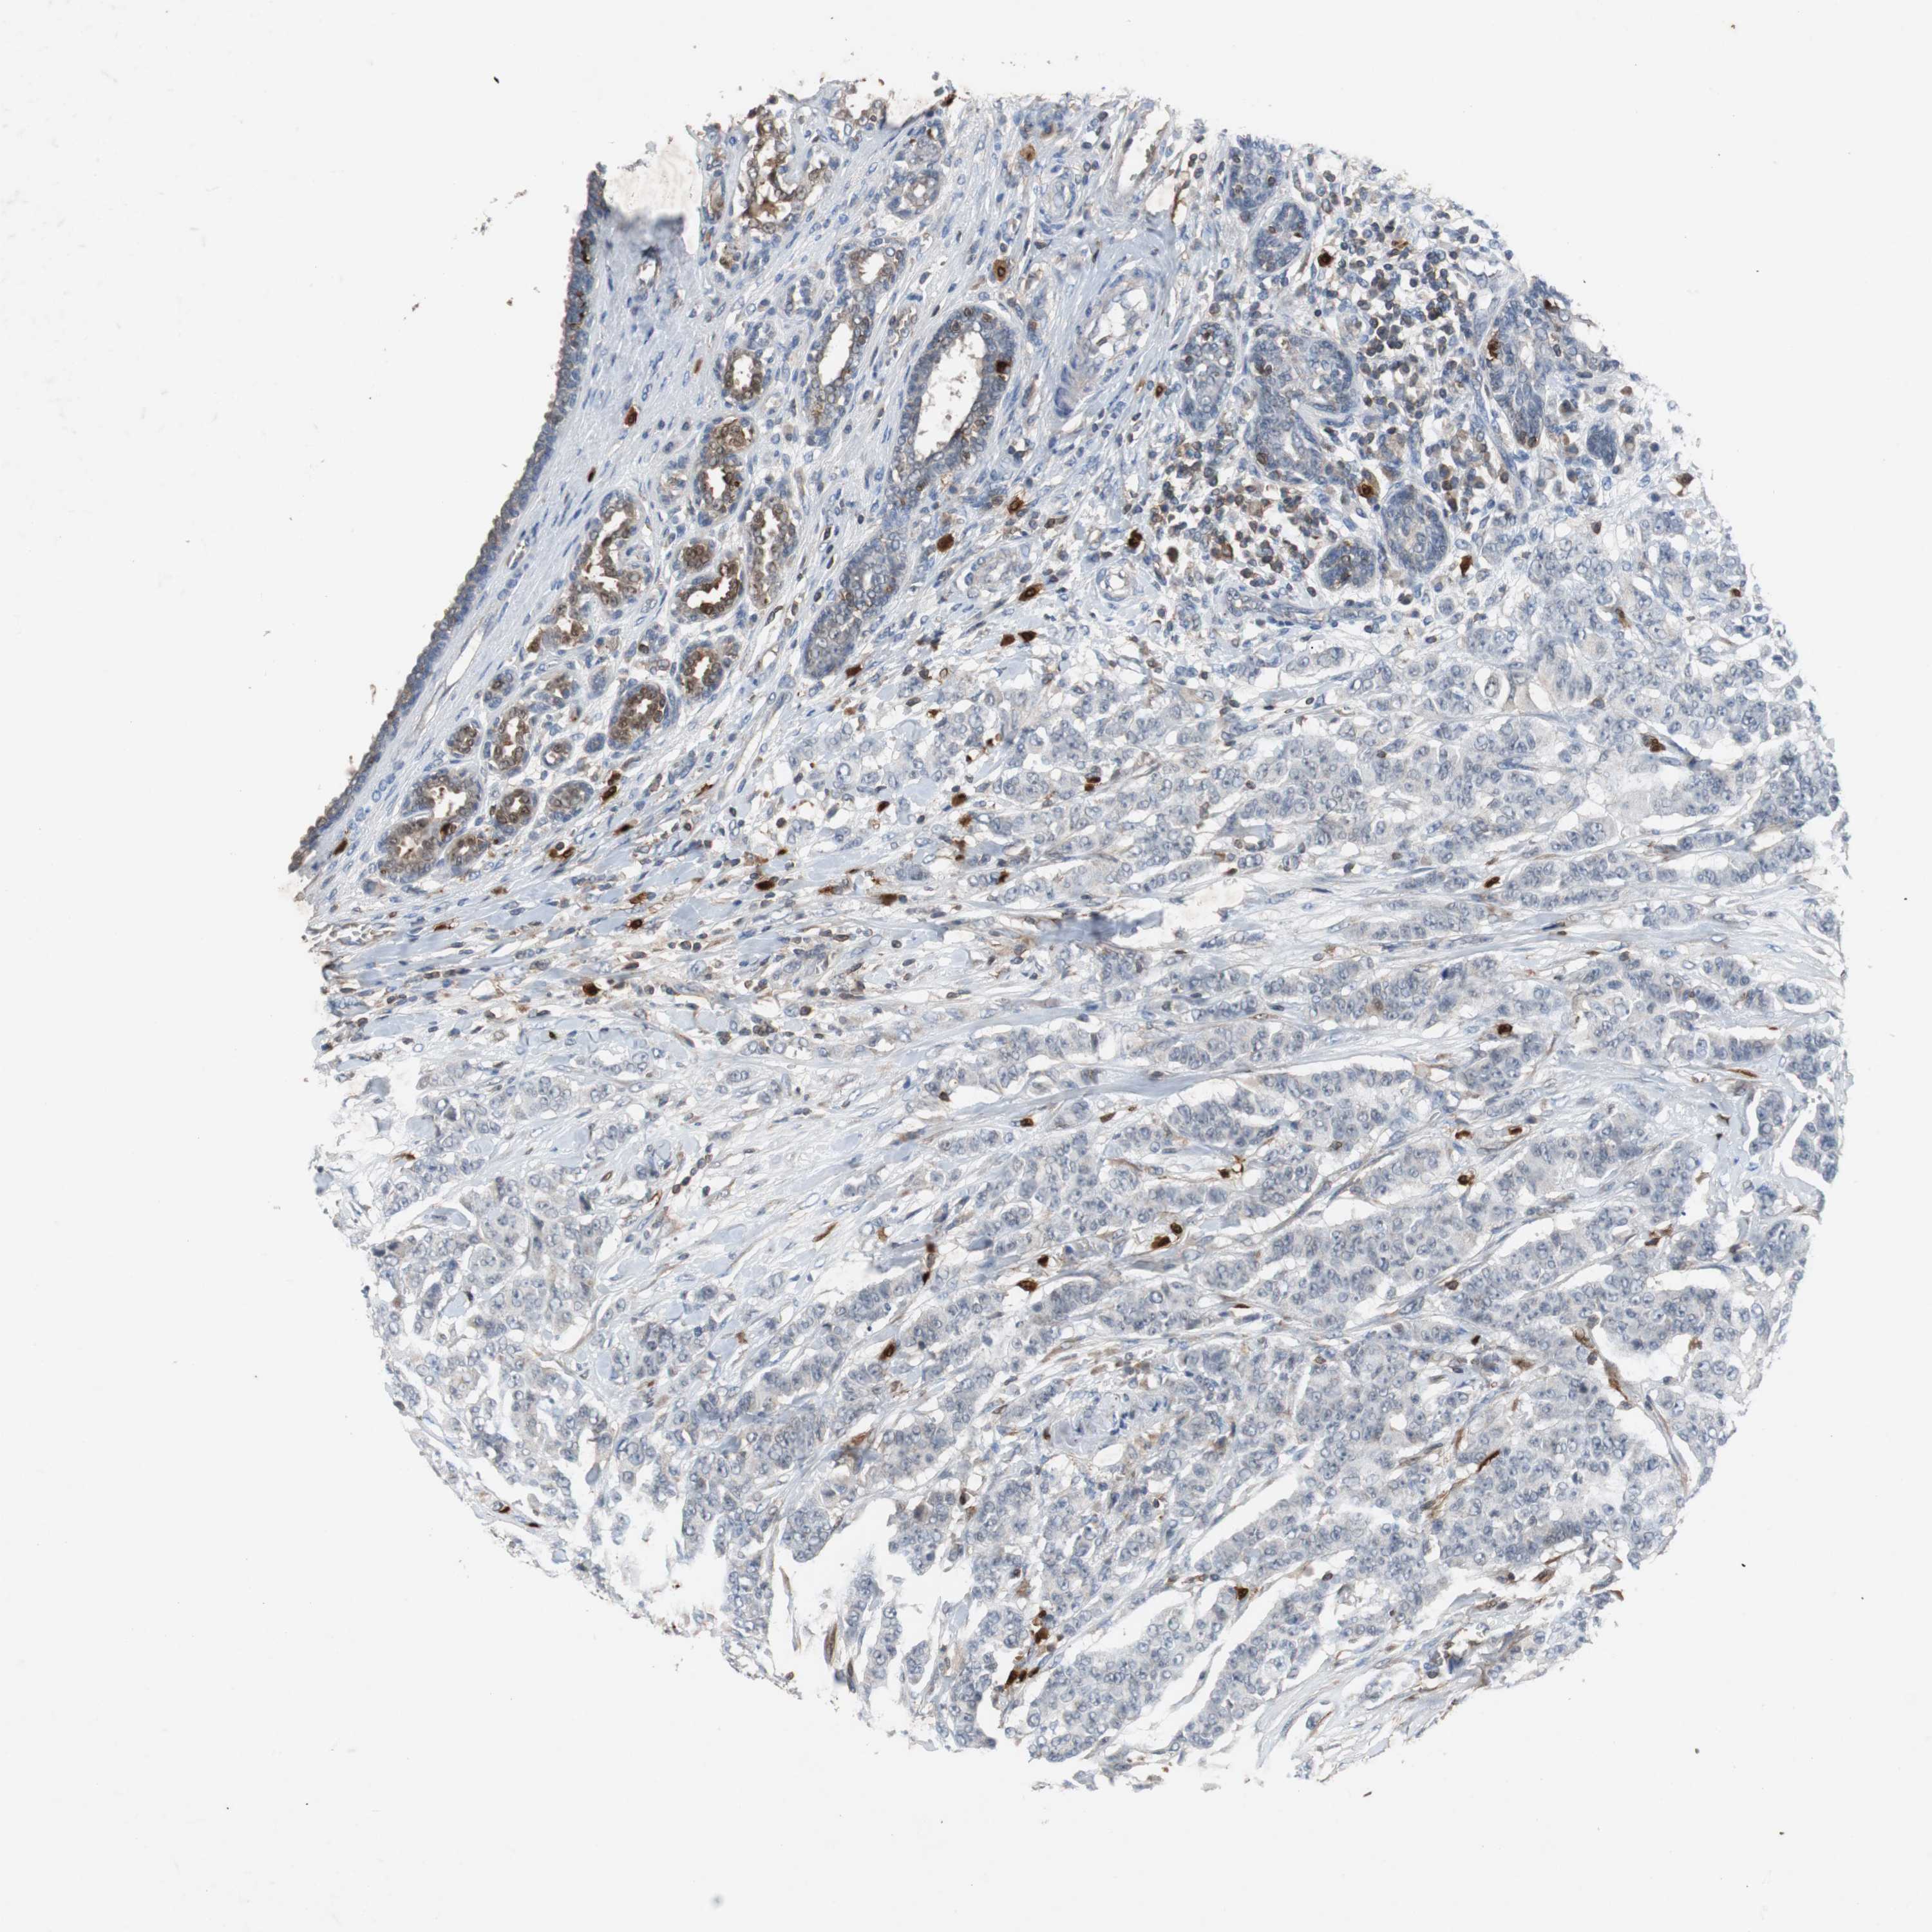

BRCA TCGA BRCA VALIDATION PROTEIN EXPRESSION

Breast cancer

Human cancer